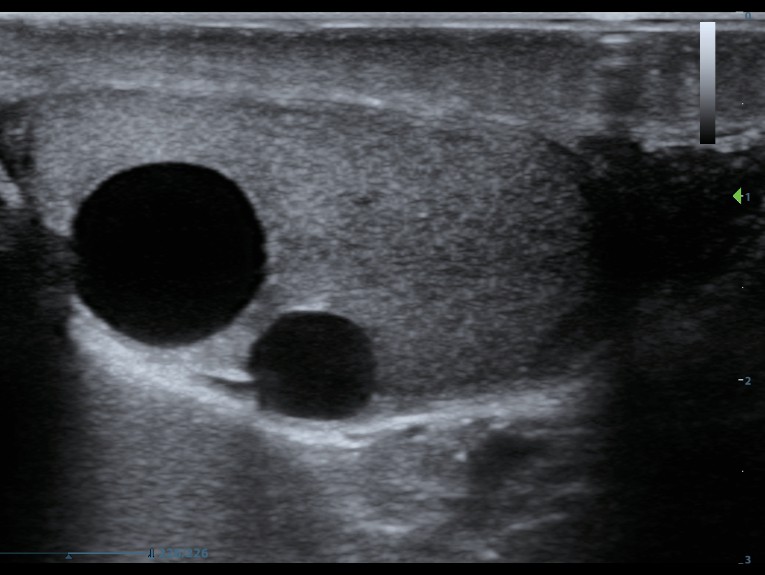

Клинические изображения